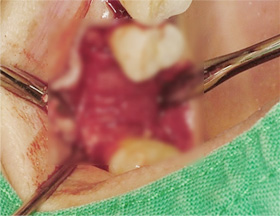

부족한 잇몸 뼈를 보충하는 뼈 이식술과

난이도 높은 상악동거상술을 진행해

안정적인 임플란트 수술을 마쳤습니다.